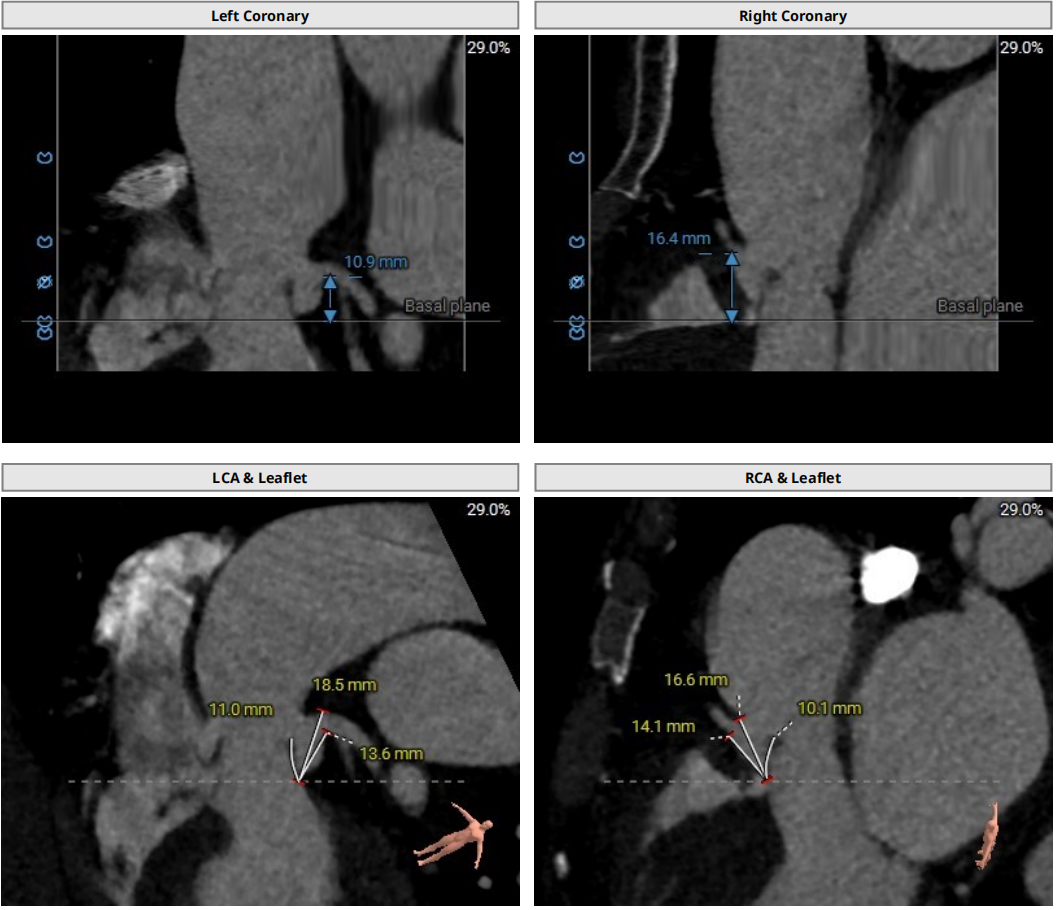

冠脉风险评估

双侧冠脉开口高度良好,瓣叶长度适中,综合瓦氏窦及窦管交界内径,冠脉风险较低。

①Type1二叶瓣,瓣环较小,无窦较大,左右窦有明显瓣叶融合脊;

②瓣叶增厚,瓣口打开受限;

③整体无钙化,AR为主。